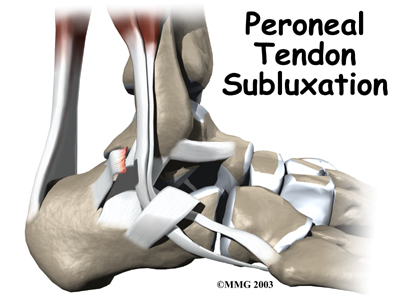

Peroneal Tendon Subluxation

The peroneals are two muscles and their tendons that attach along the outer edge of the lower leg. The peroneal tendons are enclosed in a fibrous tunnel that runs behind the outside ankle bone (the lateral malleolus). Damage or injury to the structures that form and support this tunnel may lead to a condition in which the peroneal tendons snap out of place. This condition is called peroneal tendon subluxation.